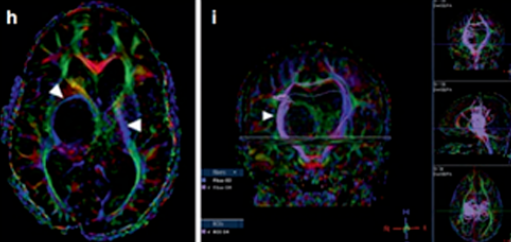

由于症状不是十分严重,且医生判断丘脑手术风险太大,小率父母一开始选择保守观察,然而,肿瘤却在悄悄跟着孩子的成长而持续增大,并“繁殖”出了多个肿瘤囊肿,此时,由于同侧内囊(负责人体肢体运动)向前外侧移位,小率已经出现了左上肢震颤,并在随后的几年中逐渐发展为急性偏瘫。

四个月后,由于小率的偏瘫没有改善,鲁特卡教授又为其行经胼胝体半球间入路及肿瘤切除术,并成功为小率切除了肿瘤。术后,小率的偏瘫改善,生长和智力发育都正常,且近期随访显示脑瘤未复发。自此,历经10年恶斗,小率最终取得胜利!